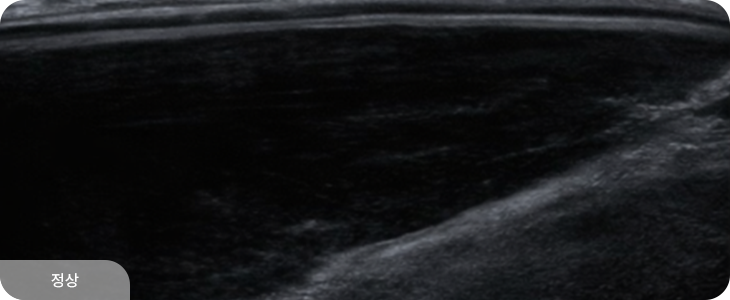

유방 확대술(보형물 삽입) 후에도 초음파 검진은 동일하게 시행할 수 있으며,

보형물 위의 유방 조직을 꼼꼼히 관찰하여 종괴나 이상 소견을 확인합니다.

보형물 자체의 파열이나 누출 여부도 초음파로 평가할 수 있어,

수술 후에도 정기적인 초음파 검진이 중요합니다.